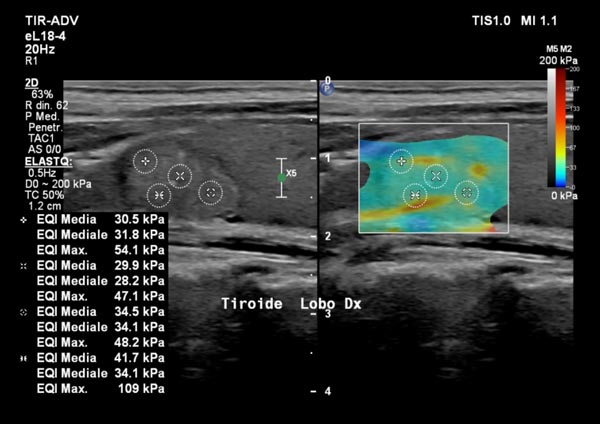

Elastosonografia tiroidea: diagnosi più precisa dei noduli?

Un altro campo in cui l’elastosonografia ha cambiato la pratica clinica è lo studio dei noduli tiroidei.«I noduli più rigidi possono essere sospetti e meritano approfondimento, mentre quelli più morbidi sono generalmente benigni. Grazie a questa metodica possiamo selezionare i casi che necessitano di un agoaspirato (FNAB) e monitorare nel tempo eventuali cambiamenti».In questo modo l’elastosonografia tiroidea diventa uno strumento prezioso per ridurre biopsie inutili e migliorare l’accuratezza diagnostica.

Un supporto prezioso alla diagnosi quindi, non un suo sostituto.

L’elastosonografia non sostituisce la diagnosi istologica, ma la integra con un’informazione aggiuntiva e non invasiva.«Il valore reale — sottolinea Ivona — è nel contesto clinico: il risultato va interpretato alla luce della storia del paziente, degli esami di laboratorio e delle immagini ecografiche tradizionali».Il vantaggio è evidente: migliorare la precisione diagnostica, ridurre i rischi e rendere il percorso di cura più personalizzato.